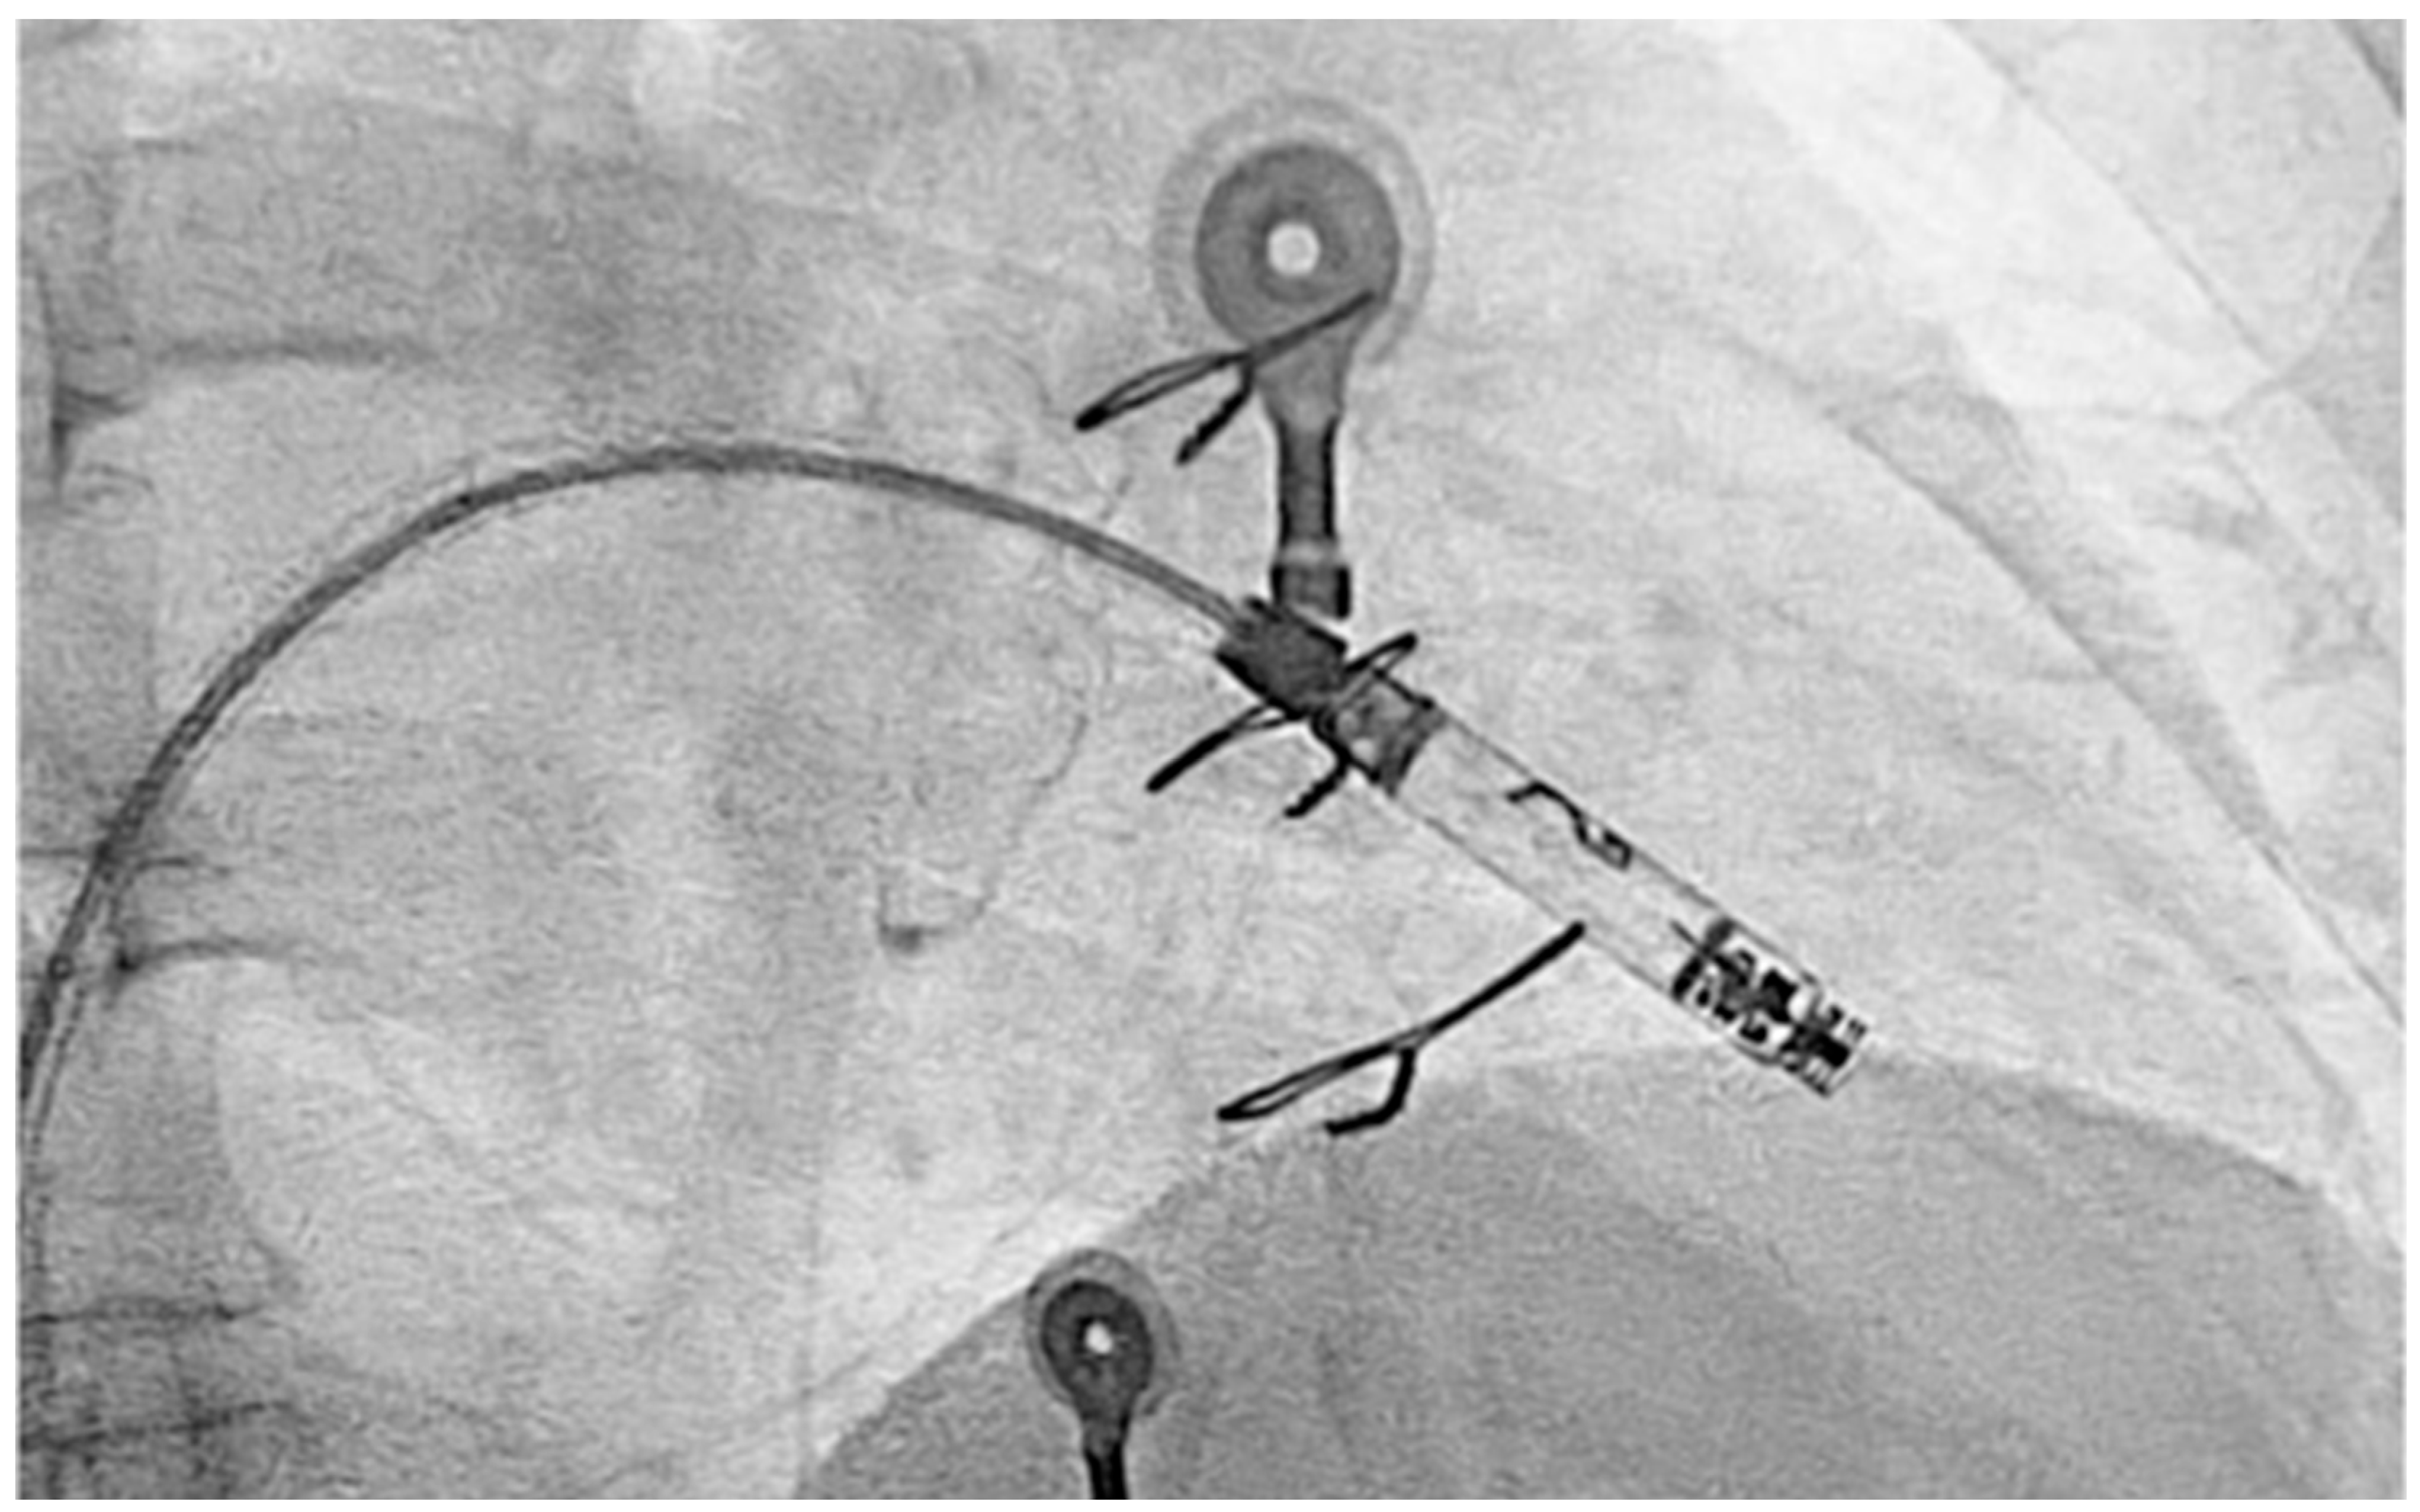

2. Case Presentation